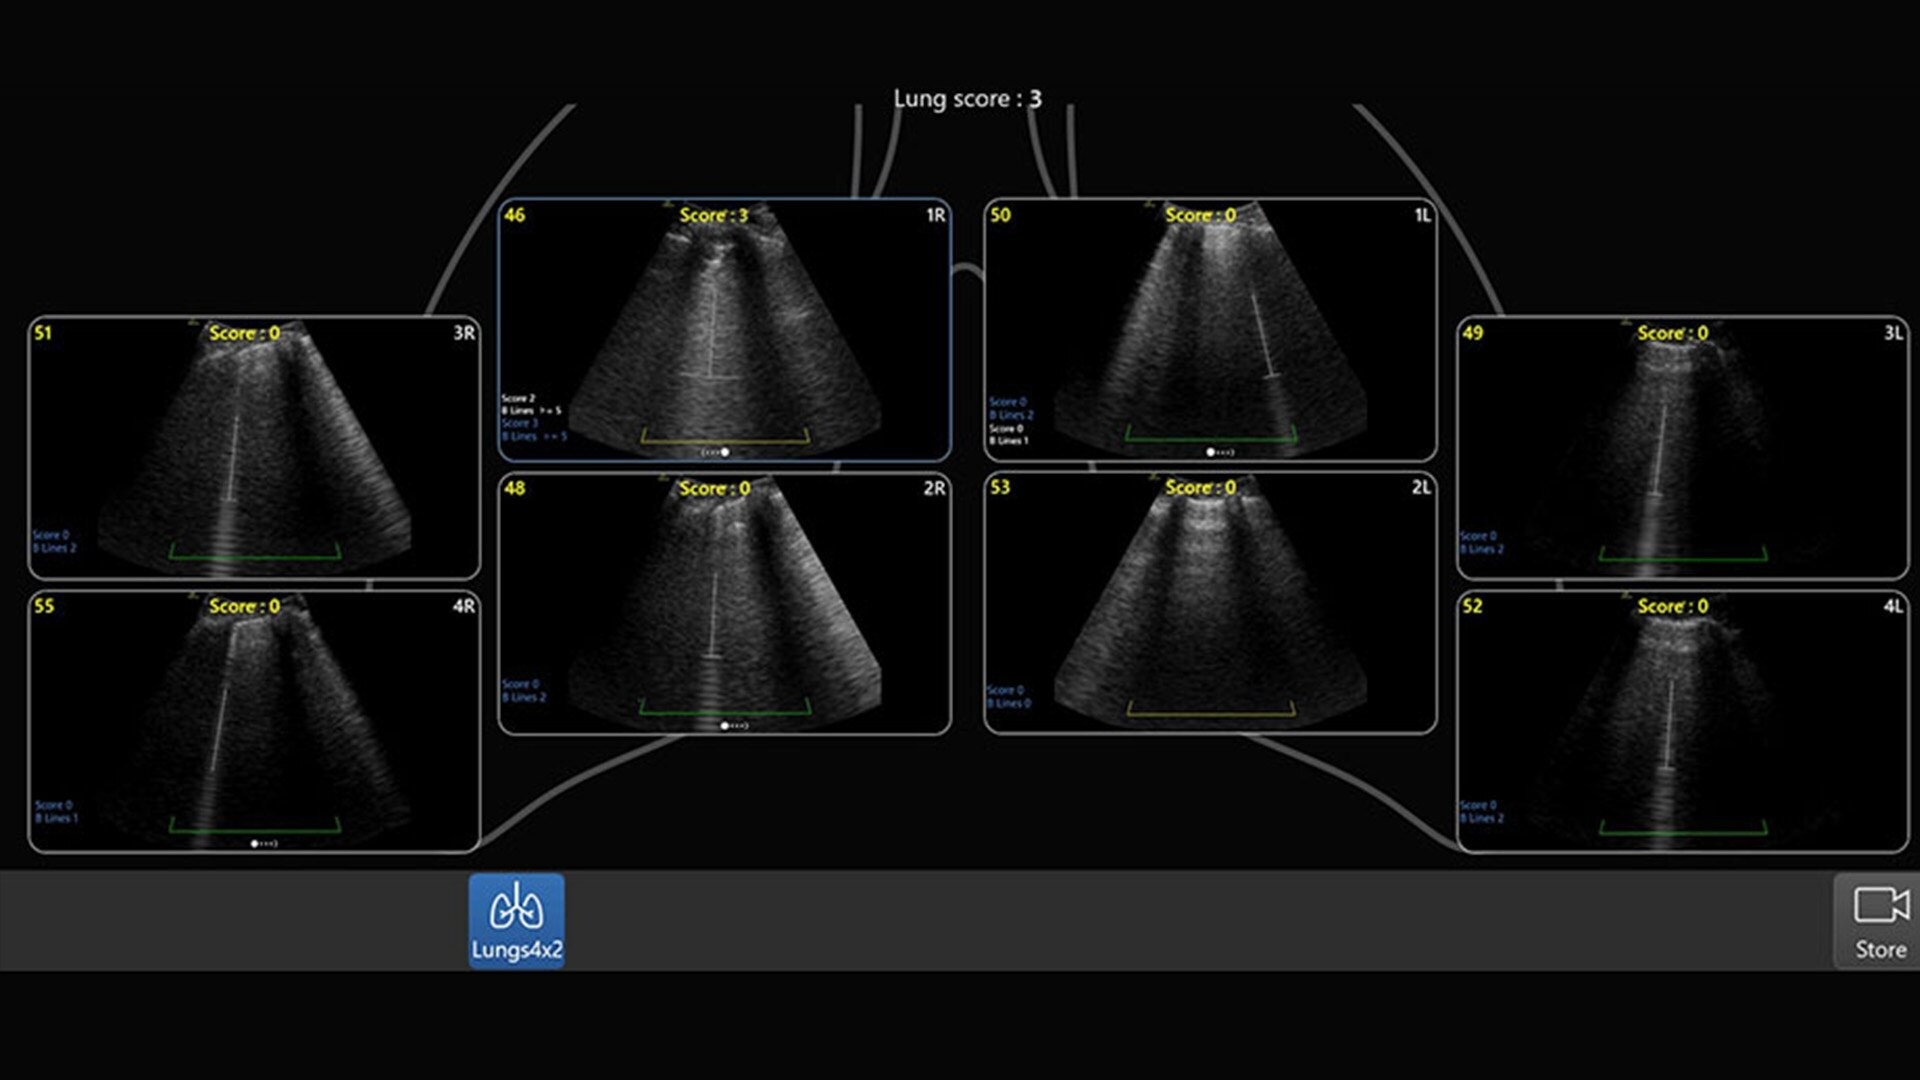

Automated tools

Simplify your workflow with AI-enabled clinical tools.

Helping drive consistency from user to user (whether one is an ultrasound novice or expert), Venue Fit features AI-enabled resources that help clinicians work smarter and more efficiently. Utilizing proprietary algorithms, we synthesize data from numerous patients to ensure accurate calculations for clinical confidence.